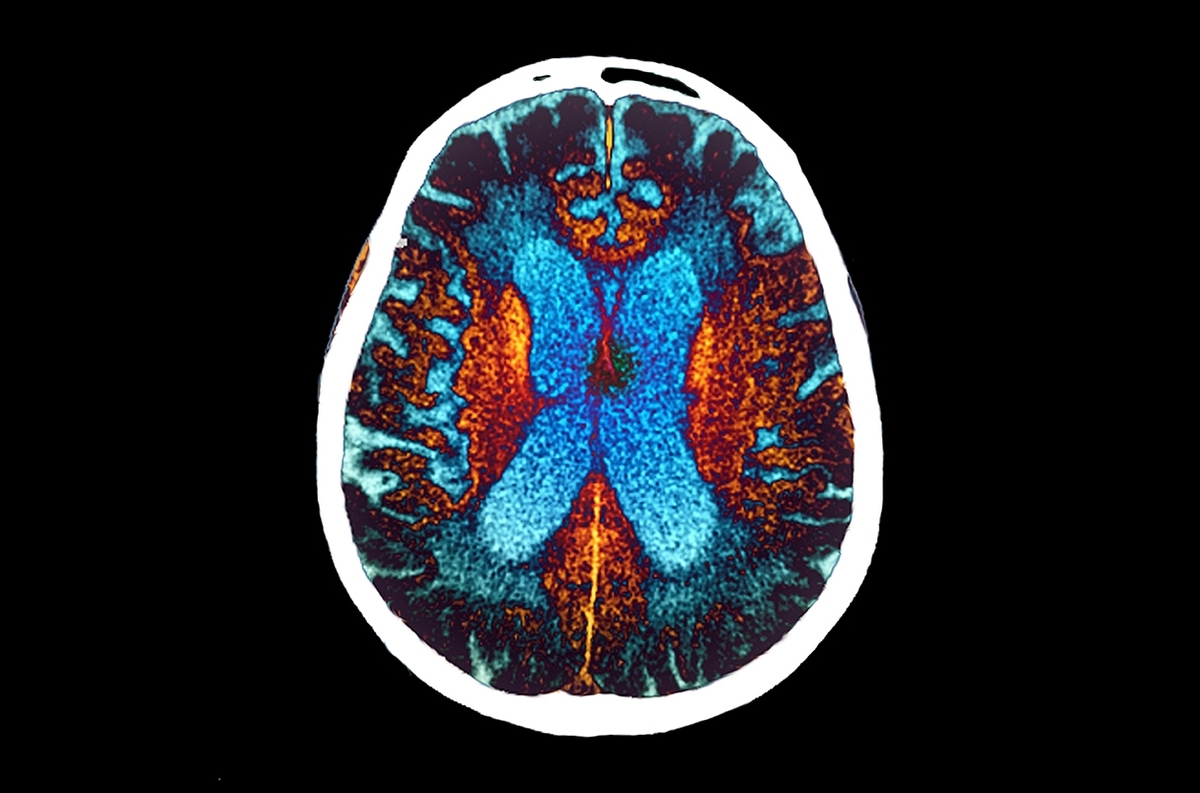

TEHRAN (ANA)- UC Irvine researchers discovered that two natural compounds can rejuvenate aging brain cells by restoring a vital energy molecule, clearing Alzheimer’s-related protein buildups, and reducing cellular stress.

Scientists at the University of California, Irvine, have uncovered a potential non-drug approach that revitalizes aging brain cells and removes the harmful protein buildup linked to Alzheimer’s disease. Their findings, published in the journal GeroScience, describe how two natural compounds, nicotinamide (a form of vitamin B3) and epigallocatechin gallate (an antioxidant found in green tea), help restore guanosine triphosphate, a key molecule that fuels energy production in brain cells. In laboratory experiments on neurons, this treatment not only reversed age-related cellular decline but also enhanced the cells’ ability to clear away amyloid protein clusters, a defining feature of Alzheimer’s.